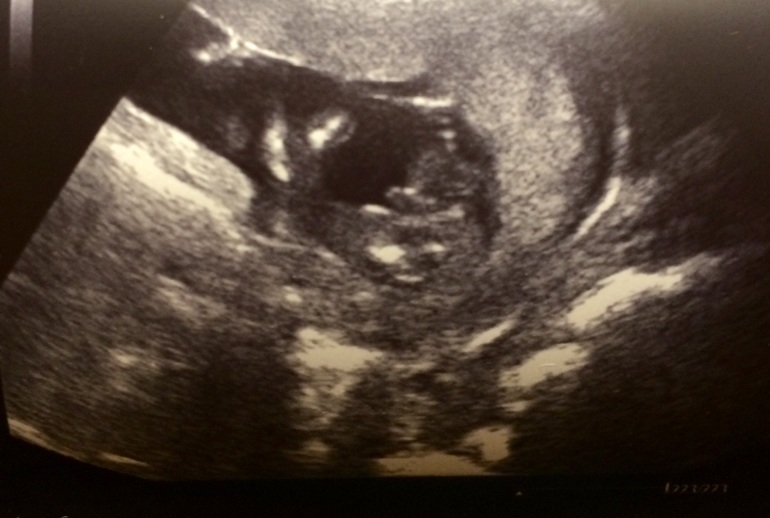

УЗИ, КТГ, доплерБыла сегодня на УЗИ, врач сделал три снимка, два понятно, но этот я совсем не могу расшифровать, очень интересно. Помогите, пожалуйста :)

На мой взгляд, малыш лежит на спинке, слева голова с ручкой, может палец сосет)))) а справа попка с ножками подогнутыми)))))

Это ж попка))) и ноги, одна согнута просто) а между ними пикулька мужская)))

если я правильно понимаю то голова слева и как будто пальчик сосет, ручка ко рту)) но я тот еще спец в узи- картинках)))на первый взгляд как будто он у вас там с игрушкой в ручках)))